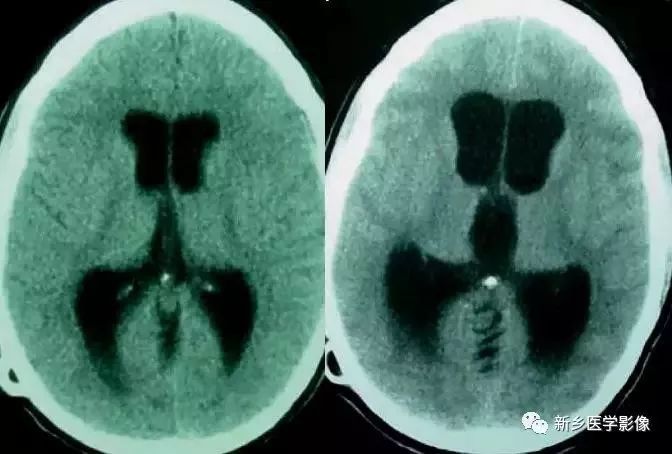

双侧侧脑室扩大

❶ 普遍性脑萎缩

普遍性脑萎缩常同时累及灰质和白质,可表现为双侧侧脑室扩大,而且是双侧侧脑室轻度对称性扩大最常见的原因。尤其多见于以脑白质萎缩为主的病人。

普遍性脑萎缩引起的侧脑室扩大通常比较对称,中线无移位。其特点是同时有脑沟、脑裂增宽等脑皮质萎缩的表现。

❷ 早产儿侧脑室扩大

在胚胎早期,侧脑室相对很大,随着发育的不断成熟,侧脑室逐渐变小,到胚胎36周时达正常大小,故早产儿常表现有双侧侧脑室轻度对称性扩大,尤其是30周前出生的早产儿。可以同时合并有或不伴有早产儿颅内出血。

❹ 大脑先天发育异常

许多种大脑发育异常均可同时表现双侧脑室扩大,包括前脑无脑裂畸形、脑裂畸形、无脑回和巨脑回等。

前脑无裂畸形(holoprosencephaly):

是指一系列位于中线程度不同的畸形,累及大脑、面部、脑于和小脑。前脑未能够分开,呈不全性或完全性,端脑和间脑无法区分。根据脑及面部畸形程度将其分为无叶型、半叶型和单叶型。

- 无叶型前脑无裂畸形:最严重,端脑半球间没有裂隙,呈马蹄形或新月形扩大的单脑室跨越中线,与背侧囊交通。丘脑互相融合,面部畸形可有两眼距离过近、独眼畸形等。往往死于胎儿或新生儿期。

- 半叶型前脑无裂畸形:在前脑可见部分裂隙, 形成不同发育程度的大脑纵裂及大脑镰。两侧大脑半球在前部未完全分开,但枕叶和 双侧侧脑室体部分离,丘脑分开不完全。三脑室和海马发育不全,胼胝体仅可见到压部,而其他部分缺如额叶和基底节前部分辨不清。临床表现有两眼距离过近、唇裂、腭裂等面部畸形,侧脑室呈单一性且明显扩大。

- 单叶型前脑无裂畸形:与正常发育脑仅有些很小的区别,如透明隔缺如或双侧额叶不完全分开。